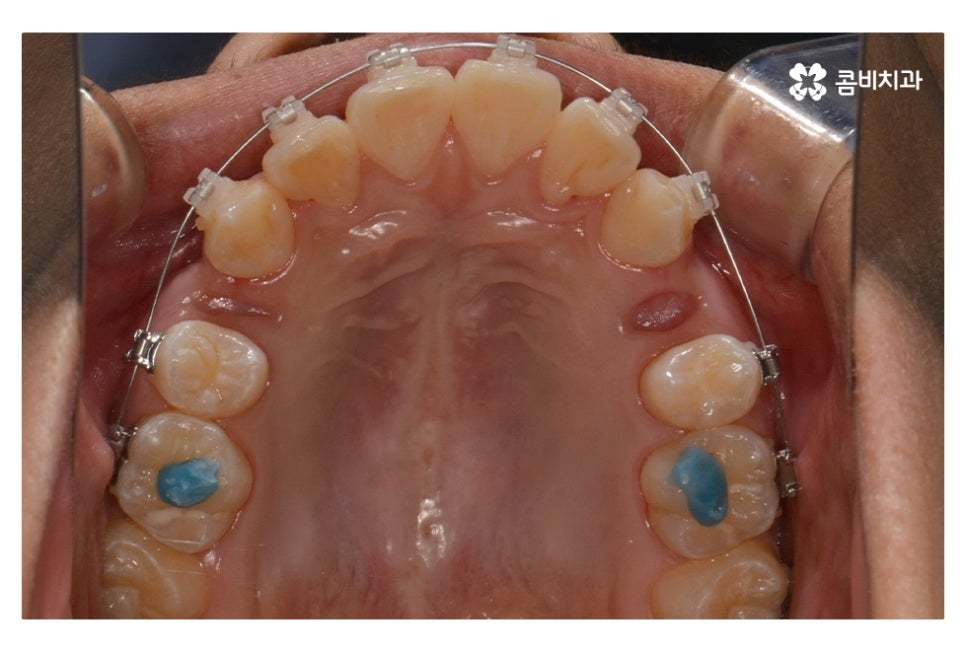

오늘 보여드릴 중학생치아교정 사례의 경우에는

악골의 위치는 정상적인 상태에서 불규칙한 치열로 인해

교정 치료를 진행한 사례라고 할 수 있어요.

위 환자분의 경우 발치가 진행된 사례로 치아의 이동 공간을

고려할 때 발치가 필요했고 환자분도 보다 나은

심미성을 위해서 동의한 상황이라고 할 수 있어요.

위 사진에서 보시면 시간이 지나면서 발치를 했던 치아의

공간이 사라지고 교정을 통해서 치열이 가지런해진 것을 확인할 수 있는데요.